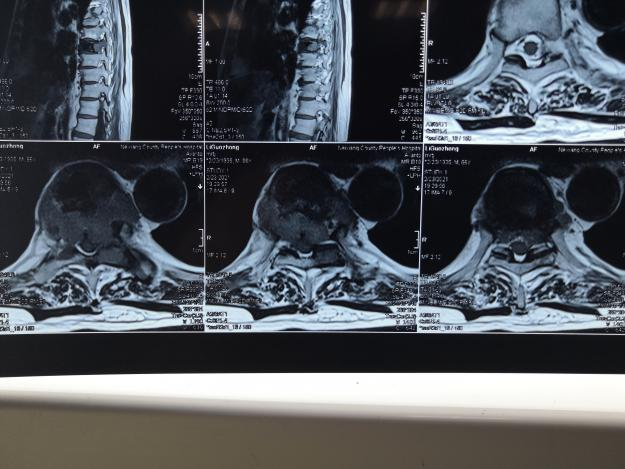

2005年7月,李女士来到医院进行复查。经过骨扫描、X线片及CT检查,她被确诊为乳腺癌胸椎骨转移。

2021年9月初,李女士突然感到双下肢不听“使唤”,来到郑州市中心医院做检查,发现胸椎的一处骨转移已经侵蚀脊髓神经。